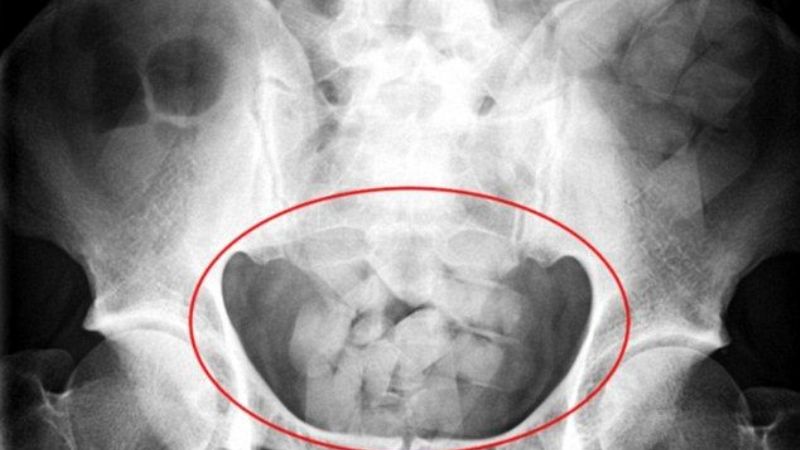

Se trata de tres mujeres de nacionalidad boliviana que fueron detenidas en la Terminal de Ómnibus catamarqueña cuando intentaban viajar a la provincia de San Juan. Las tres bolivianas eran "mulas” que traficaban estupefacientes ilegales dentro de su organismo.